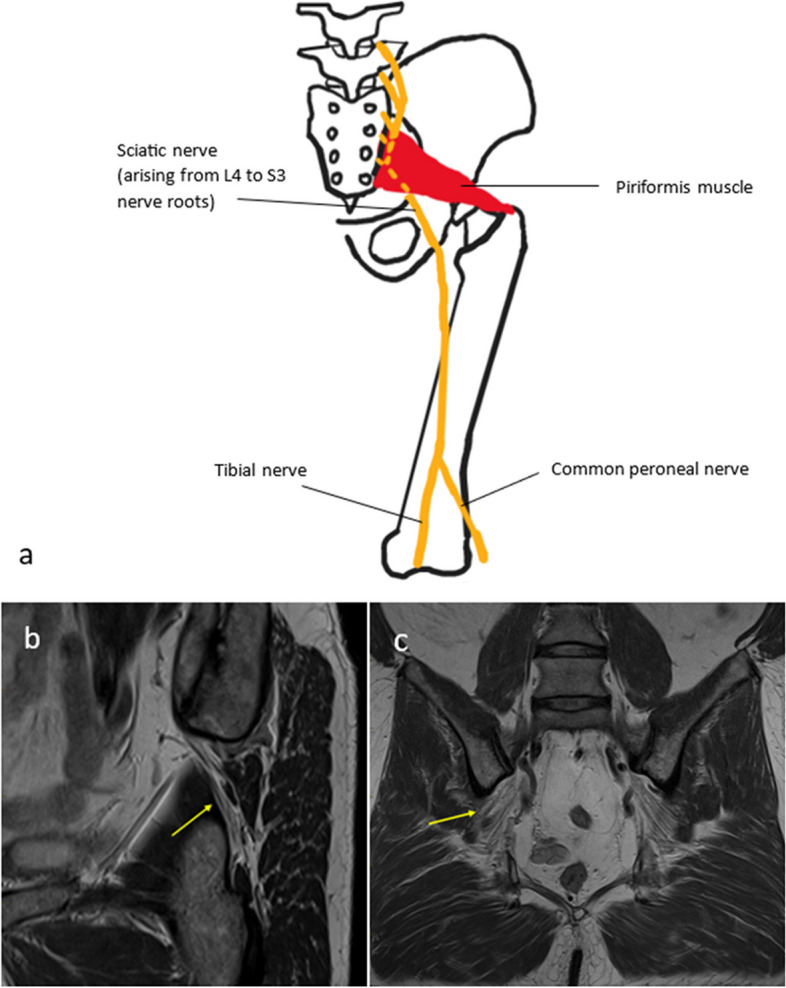

يشير عرق النسا أو ألم العصب الوركي إلى مجموعة من الأعراض التي تحدث عند ضغط أو تهيج العصب الوركي وهو أطول عصب في الجسم يمتد من أسفل الظهر عبر الأرداف وصولا إلى الساقين. غالبا ما يحدث بسبب الانزلاق الغضروفي أو تضيق العمود الفقري أو متلازمة الكمثري. ينتج عن ذلك ألم حاد أو حارق ينتشر أسفل الساق مصحوبا غالبا بتنميل أو وخز أو ضعف عضلي. على سبيل المثال تعد متلازمة الكمثري سببا مهما لضغط العصب الوركي حيث يمر العصب عبر عضلة الكمثري أو تحتها وأي تضخم أو تشنج في هذه العضلة يمكن أن يسبب تهيج العصب. لذلك يعد عرق النسا من أهم أسباب تنميل الرجل وعلاجها يعتمد على معالجة السبب الأساسي للضغط.